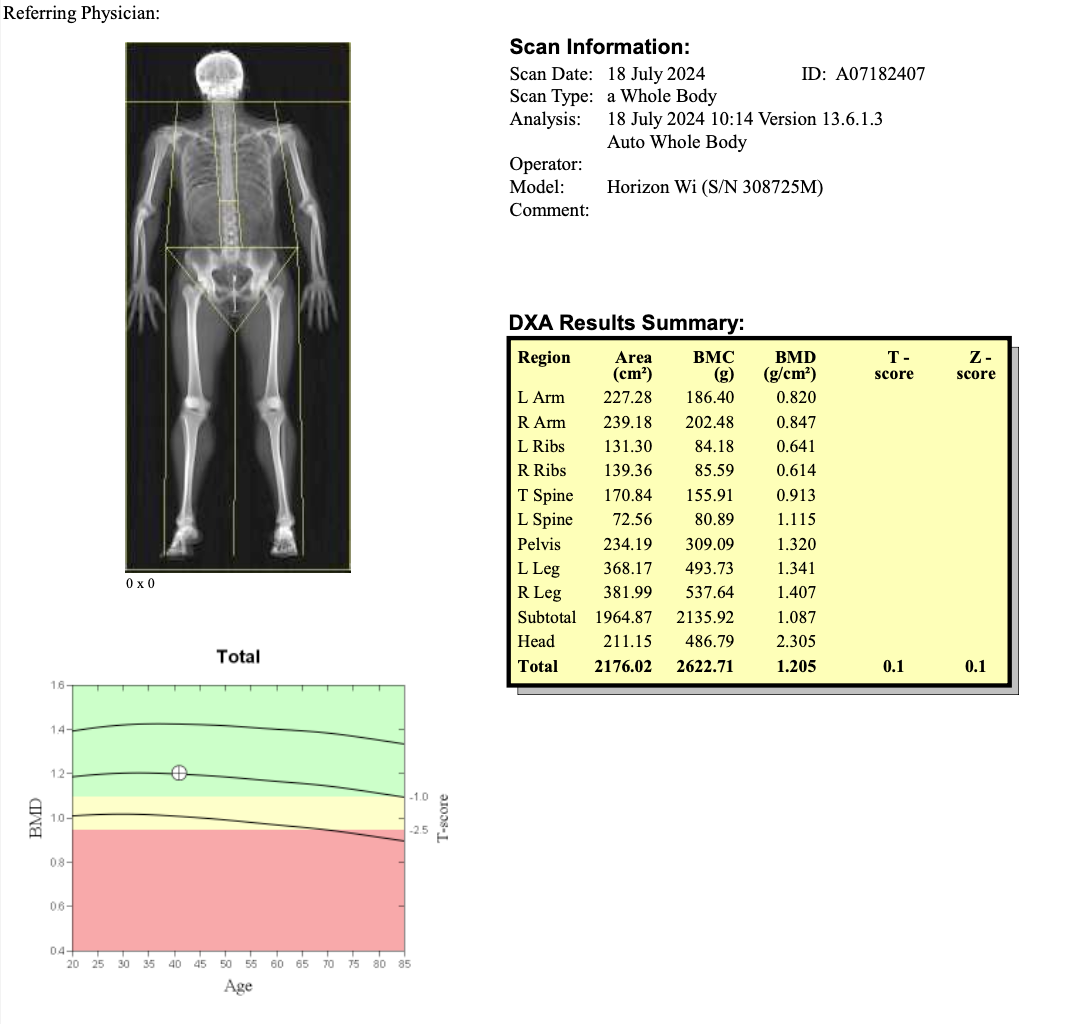

Example Report: